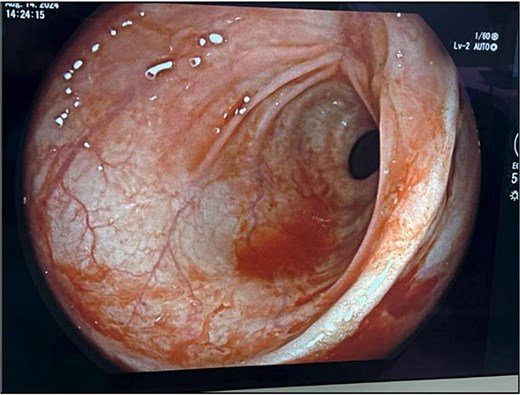

The patient’s leukocytosis resolved during hospitalization, and she was discharged on hospital day 5 with dietary modifications, including a low-fiber diet. At 4-week follow up, flexible sigmoidoscopy demonstrated near-complete healing of the rectal perforation, with only minimal residual mucosal disruption (Fig. 3). By 6 weeks post-injury, follow-up flexible sigmoidoscopy confirmed complete mucosal healing and restoration of normal rectal wall architecture, though mild rectal stenosis persisted (Fig. 4). The patient remained asymptomatic with resolution of her initial symptoms.

Follow-up flexible sigmoidoscopy at 4 weeks showing near-complete healing of the rectal perforation, with a small residual mucosal disruption.

Flexible sigmoidoscopy at 6 weeks demonstrating complete mucosal healing and re-epithelialization at the prior perforation site, with no residual defect or inflammation.